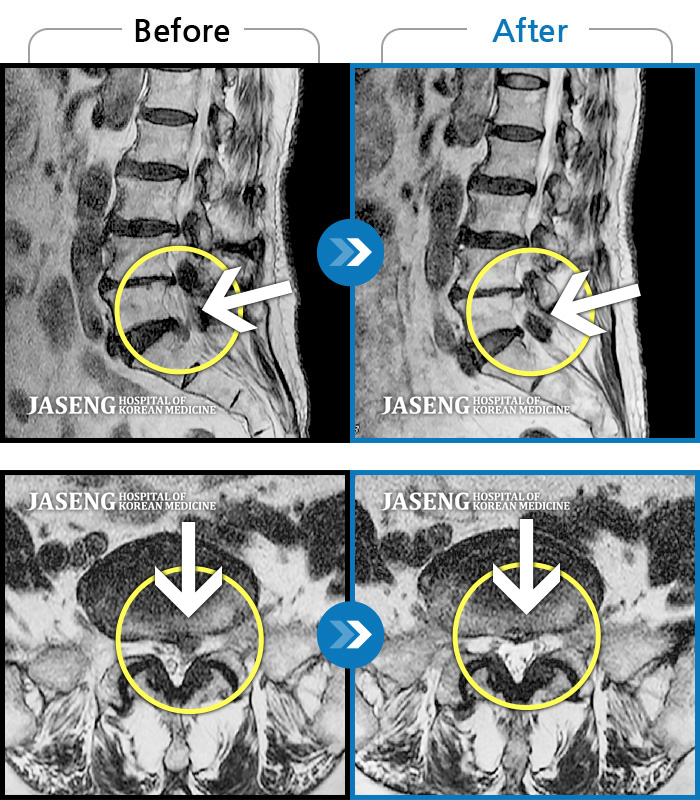

허리디스크

많이 본 사례

인천 · 조남훈 원장

계속 아파서 일을 일주일에 2번밖에 못해요.

촬영시기

2019.11.23 ~ 2023.12.15

2023.12.20